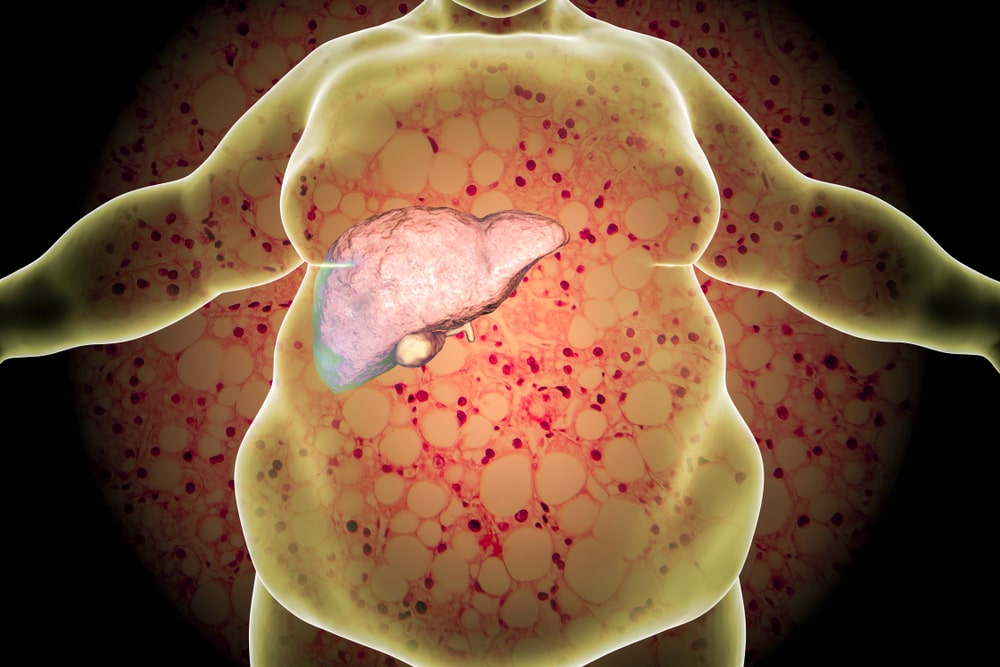

非酒精性脂肪肝(脂肪肝)是最常見的慢性肝病之一,現時香港約有25%人口受到脂肪肝的影響,而且患者數目有上升趨勢。

當我們從日常飲食中攝取過量熱能,脂肪便會於肝臟 漸漸積聚。當脂肪含量佔整體肝臟的5-10%以上,醫 學上稱之為「脂肪肝」。

脂肪肝與代謝性疾病有著密切的關係,研究指脂肪肝 患者罹患心血管病及肝病相關死亡會較一般人高。三 高(高血糖、高血壓、高血脂)和中央肥胖(男士腰 圍36寸以上,女士腰圍32寸以上)人士,都是患上脂 肪肝的高危一族。